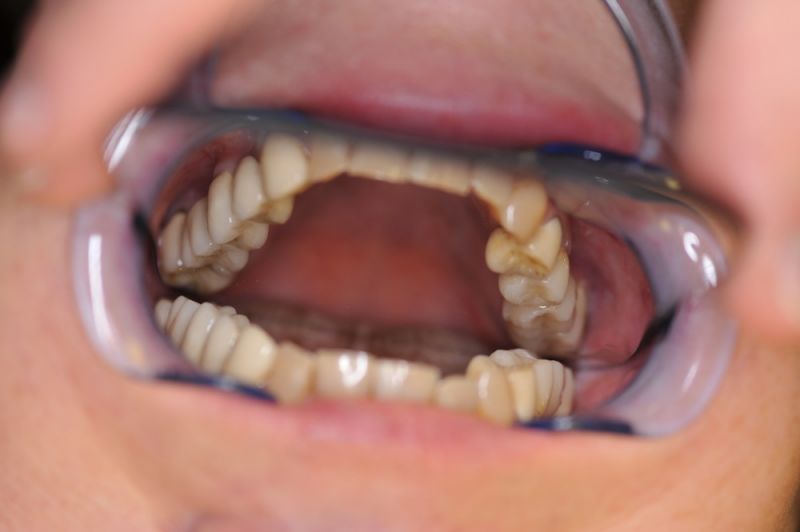

Es war eine Kombination aus Schmerzen bis an die Suizidgrenze, beschränkten wirtschaftlichen Möglichkeiten, sehr stark eingeschränkten Möglichkeiten der für Implantate zur Verfügung stehenden Knochenverhältnisse in einem stark atrophierten Unterkieferseitenzahnbereich und zudem dann auch noch durch auftretenden Problemen bei der Implantatinsertion und nachfolgenden Versorgung der Implantate.

Alle 3 Monate Recall! Das ist jetzt Pflicht für diese Patientin und zwar so lange, so lange sie mit dieser Arbeit durch die Gegend laufen möchte! Und eiserne Disziplin bei der Mundhygiene!